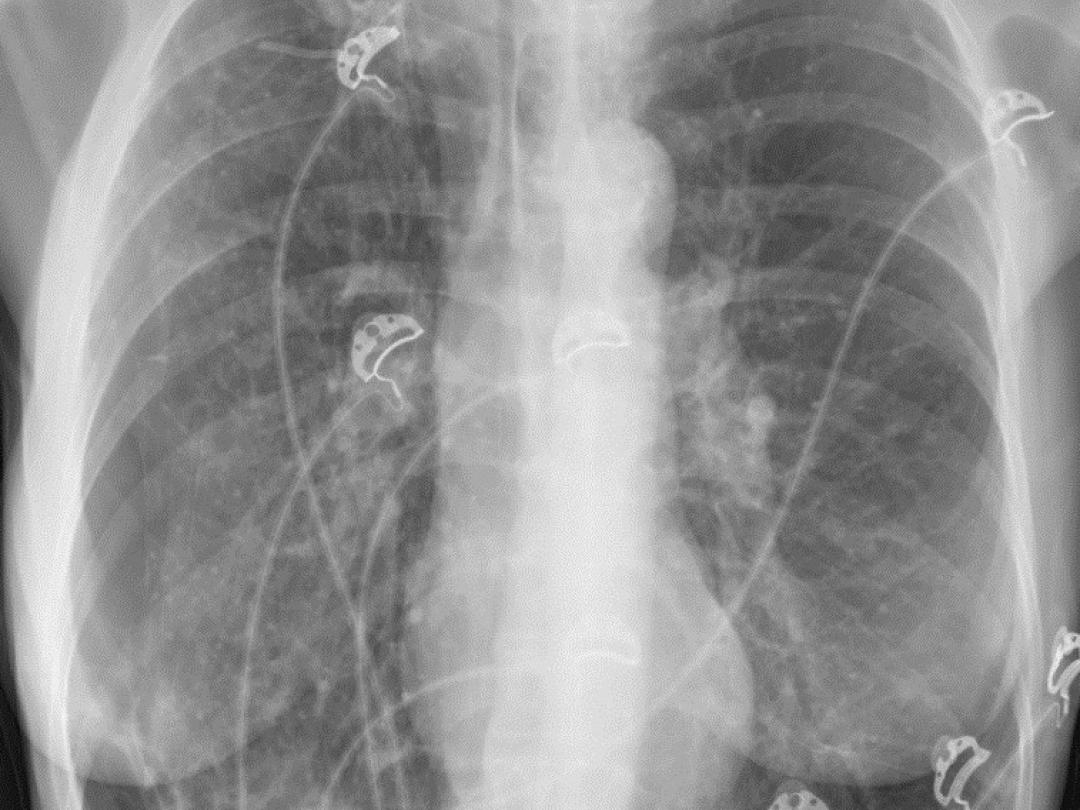

Röntgenfoto van een ribbenkast.

Een 54-jarige vrouw kwam op de SEH vanwege plotselinge dyspneu en pijn aan rechterzijde van de thorax. In de voorgeschiedenis had zij onder andere een pneumothorax aan rechterzijde waarvoor zij was behandeld met pleurodese, een voor maligniteit verdachte afwijking in de rechter bovenkwab waarvoor zij was bestraald en COPD in stadium GOLD 4 met emfyseem. Wij zagen een dyspnoïsche vrouw met een ademfrequentie van 24 per minuut en een zuurstofsaturatie van 99%. Zij had geen abdominale klachten. Bij longauscultatie was er verminderd ademgeruis aan de rechterzijde. Bij onderzoek van het abdomen was sprake van hypersonore percussie; bij palpatie was…